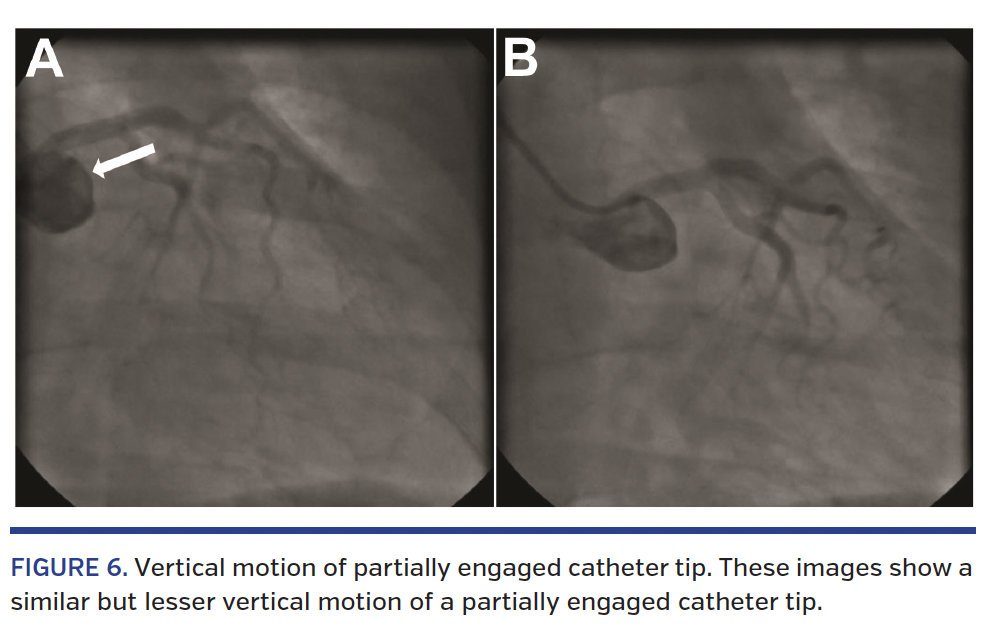

Although coronary engagement is an hourly phenomenon in the cardiac catheterization laboratory, the characteristic rhythmic motion of the catheter tip, diagnostic of successful and stable engagement, has not been well described or correlated with advancements in echocardiographic myocardial mechanics. This case of a 56-year-old woman with normal coronaries displays the side-to-side motion of the unengaged JL4 catheter (Figure 1; Video 1) followed by the rhythmic up-and-down, piston-like movements of the catheter tip after engagement (Figure 2; Video 1) up in diastole and down in systole. The side-to-side motion is likely caused by the pulsatile systolic jet of blood from the ventricle across the aortic valve. As seen in standard echocardiography, the base of the ventricle contracts and moves downward during systole, whereas the apex stays stationary (Figure 3; Video 2). The velocity of this motion is further quantified via tissue Doppler imaging (Figure 4). The movement is primarily that of base moving to apex, as in a horizontal heart, the catheter tip will primarily move side to side, from base to apex (Figure 5; Video 3). A partial engagement of the ostium can be suggested without contrast injection, but not categorically separated from complete engagement, by the catheter tip motion alone (Figure 6, Video 4) because the sinus of Valsalva also moves vertically with the base of the ventricle, although the movement is slightly less marked.